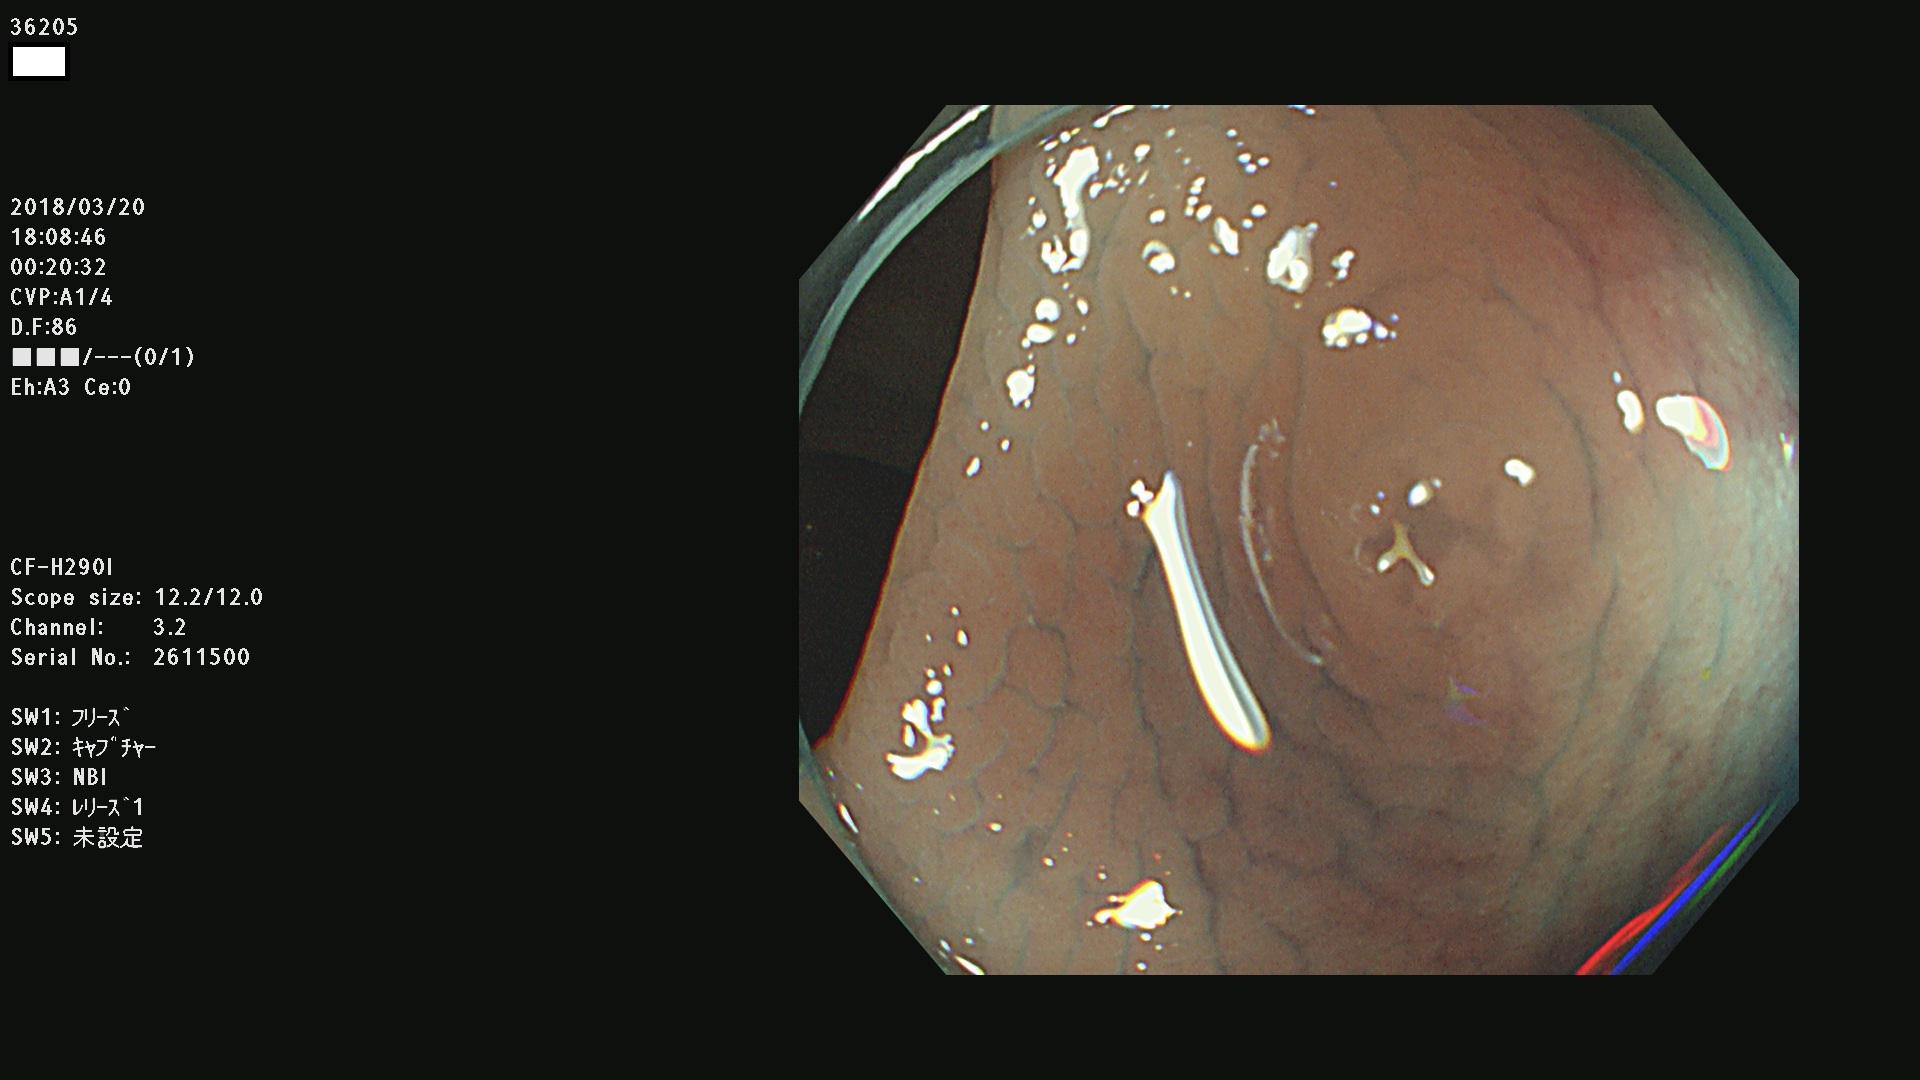

36201 36202 36203 36205 36207 36209 36210 36212 36213 36214 36215 36217 36220 36221 36222 36224 36225 36226 36227 36229 36230 36231 36232 36235 36236 36238 36240 36243 36244 36246 36247(SSAPのみ。SPS) 36248 36249 36251 36252 36253 36254 36255 36256 36257 36258 36259 36261 36262 36264 36265 36267 36269 36270 36272 36274 36275 36276 36279 36280 36281 36283 36285 36288 36289 36291 36292 36295 36296 36297 36299

発見困難で危険性の高い平坦型病変(上記100名より抽出)